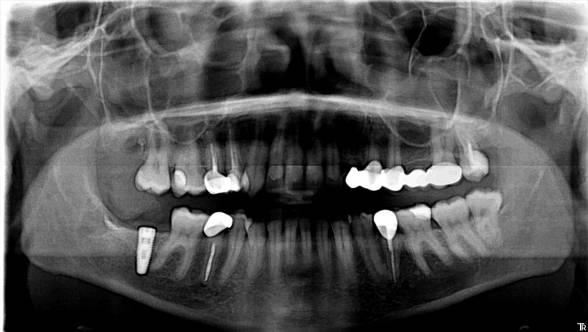

На контрольной рентгенограмме, в области раннее установленного имплантата, спустя более года, патологий не наблюдается. Пациентка не предъявляет жалоб.

Данное прошедшее заболевание и проведённая операция, не явились противопоказанием, для полноценной ортопедической реабилитации при концевом дефекте, с помощью имплантации.